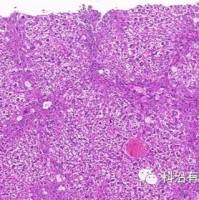

2)6周后或肿瘤大小达到伦理学终点,摘取移植瘤,福尔马林固定,石蜡包埋,进行HE染色。

裸鼠乳腺癌原位移植瘤模型